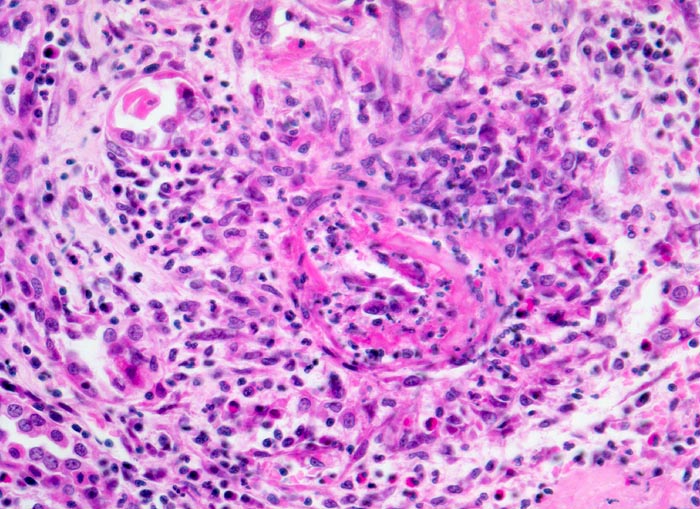

Aktive Vaskulitis: Infiltration und/oder Destruktion der Gefässwand durch ein Entzündungsinfiltrat. Intraluminale Fibrinthromben oder intramurale Fibrinablagerungen (fibrinoide Nekrose).

Befallen sind prärenale und grössere intrarenale Nierenarterienäste bei meist fehlender Beteiligung der Arteriolen und definitionsgemäss fehlendem Befall der glomerulären Kapillaren. Die betroffenen Gefässe zeigen segmentale transmurale oft durch Thrombosierung komplizierte Wandnekrosen mit initial granulozytenreichem Infiltrat. Im Verlauf werden die Nekrosen durch Granulations- und Narbengewebe organisiert. An grossen Arterien kann dies zu Knotenbildungen und Aneurysmata führen. Oft findet man in ein und demselben Gefäss frische Nekrosen neben reparativen Veränderungen und Narben. Das übrige Nierengewebe zeigt als Folge der Vaskulitis Kollapsglomerula, Infarkte und ischämische Tubulusatrophie mit begleitender interstitieller Fibrose und Entzündung.